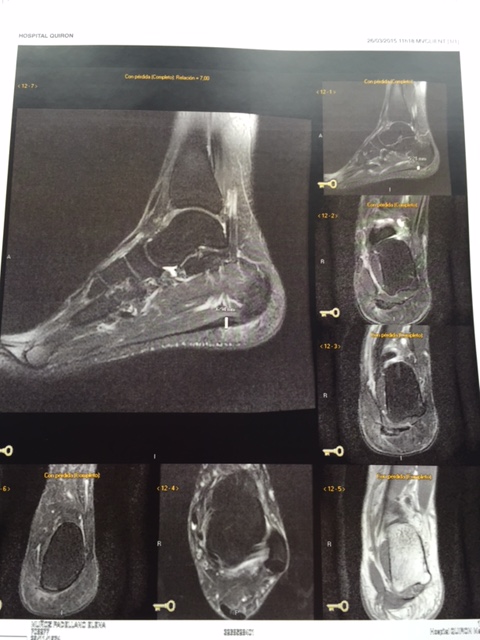

Lo del pie, fastidiada pero sabía que me iban a parar. Dicen que el engrosamiento es más de lo que esperaban, pero es estraño porque me debería doler mucho más. Tengo que mirar la resonancia que me hicieron del otro pie hace 2 años para ver si realmente esa zona yo la tengo más gruesa de lo normal. Me van a hacer un intensivo en el fisio. Dentro de un mes, me van a inflitrar (a finales de abril)